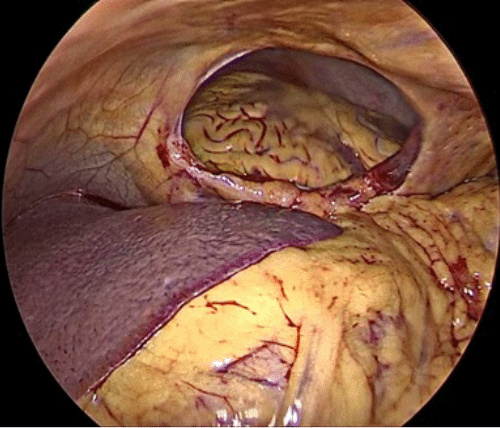

As the patient was hemodynamically stable and there was no internal bleeding, we decided to proceed with laparoscopic surgery with the possibility of conversion at any time if the patient became hypotensive. The patient signed the consent form and underwent surgery after proper preparation. Following induction of anesthesia, bilateral 28-Fr chest tubes (Polymed Medical Devices, Haryana, India) were inserted; 200 mL (0.2 × 10-3 m3) of blood was drained from the left tube, while the right tube did not have any observable output. The patient was stable enough to proceed to laparoscopic surgery. The abdominal cavity was approached from a supraumbilical incision using the open Hasson technique. Two 5-mm trocars (Covidien, Mansfield, MA, USA) were inserted from the left and right subcostal areas under laparoscopic visualization. Upon entering the abdominal cavity, we observed a central diaphragmatic defect communicating with the pericardial space. The heart was seen beating through the 8 cm diaphragmatic defect, with no perceptible damage or free blood in the abdomen (Figure 4). There was a small injury on the edge of the left lobe of the liver without any active bleeding, the stomach was mildly distended with no perceptible injury, there was no splenic injury, and the bowel and mesentery looked normal and healthy. The defect was closed by running a 2-0 tension-free, nonabsorbable suture; three interrupted stitches were placed along the suture line for reinforcement, and a composite mesh of 10 × 15 cm (Symbotex™ composite mesh; Covidien, Walpole, MA, USA) was used to cover the repair and was fixed to the diaphragm with absorbable tacks (AbsorbaTack™; Covidien, Walpole, MA, USA) (Figure 5).

Figure 4. Intraoperative View of Ruptured Central Diaphragm with Clear Window to Pericardial Space. A) Remote and B) Close Views. Published with Permission